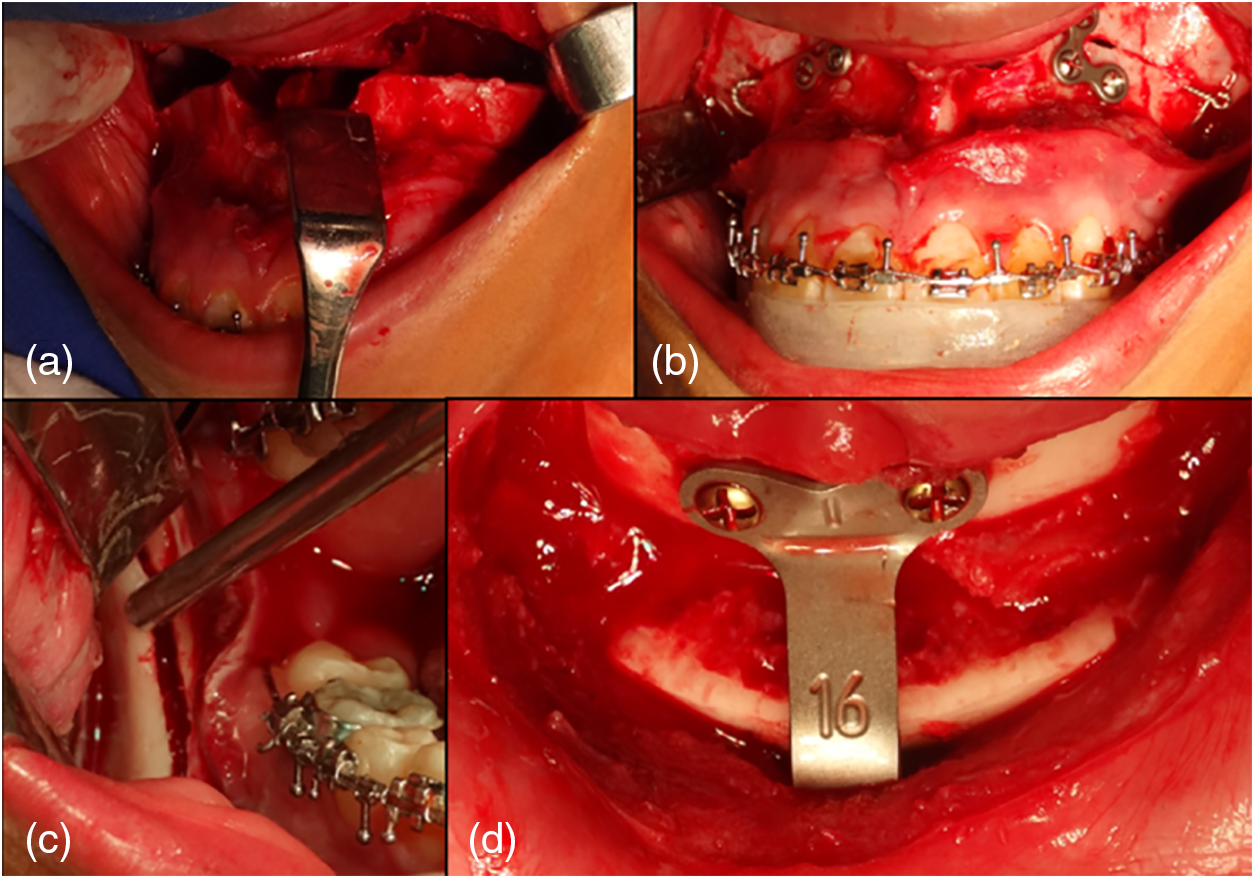

Postoperative: For one week after surgery, the patient wore a splint, as well as class II elastics (from the upper canine to the first lower molar) with a resistance of 6 1/4 oz. A follow-up radiograph was obtained one week after surgery, including lateral, panoramic, and postero-anterior cephalometry (Fig. 4).

Fig. 4. Orthognathic surgery a) Lefort I osteotomy, b) Intermediate splint placement, c) OSRAM to advance and rotate counterclockwise the mandible body, and d) Advancement menthoplasty with iliac crest graft.

Le Fort I osteotomy: A 5 mm mandibular intrusion was performed with a mandibular response. Surgical planning was performed considering a previous cephalometric prediction and performing the procedure (Figs. 2a, 2b).

OSRAM: This surgical procedure was performed to advance the mandible by 7 mm and to rotate the body of the mandible in a counterclockwise direction, with an open posterior bite of 3 mm to achieve a greater projection of the chin (Fig. 3c).

A mentoplasty was performed to achieve a 6 mm advancement of the mandible (Fig. 3d).